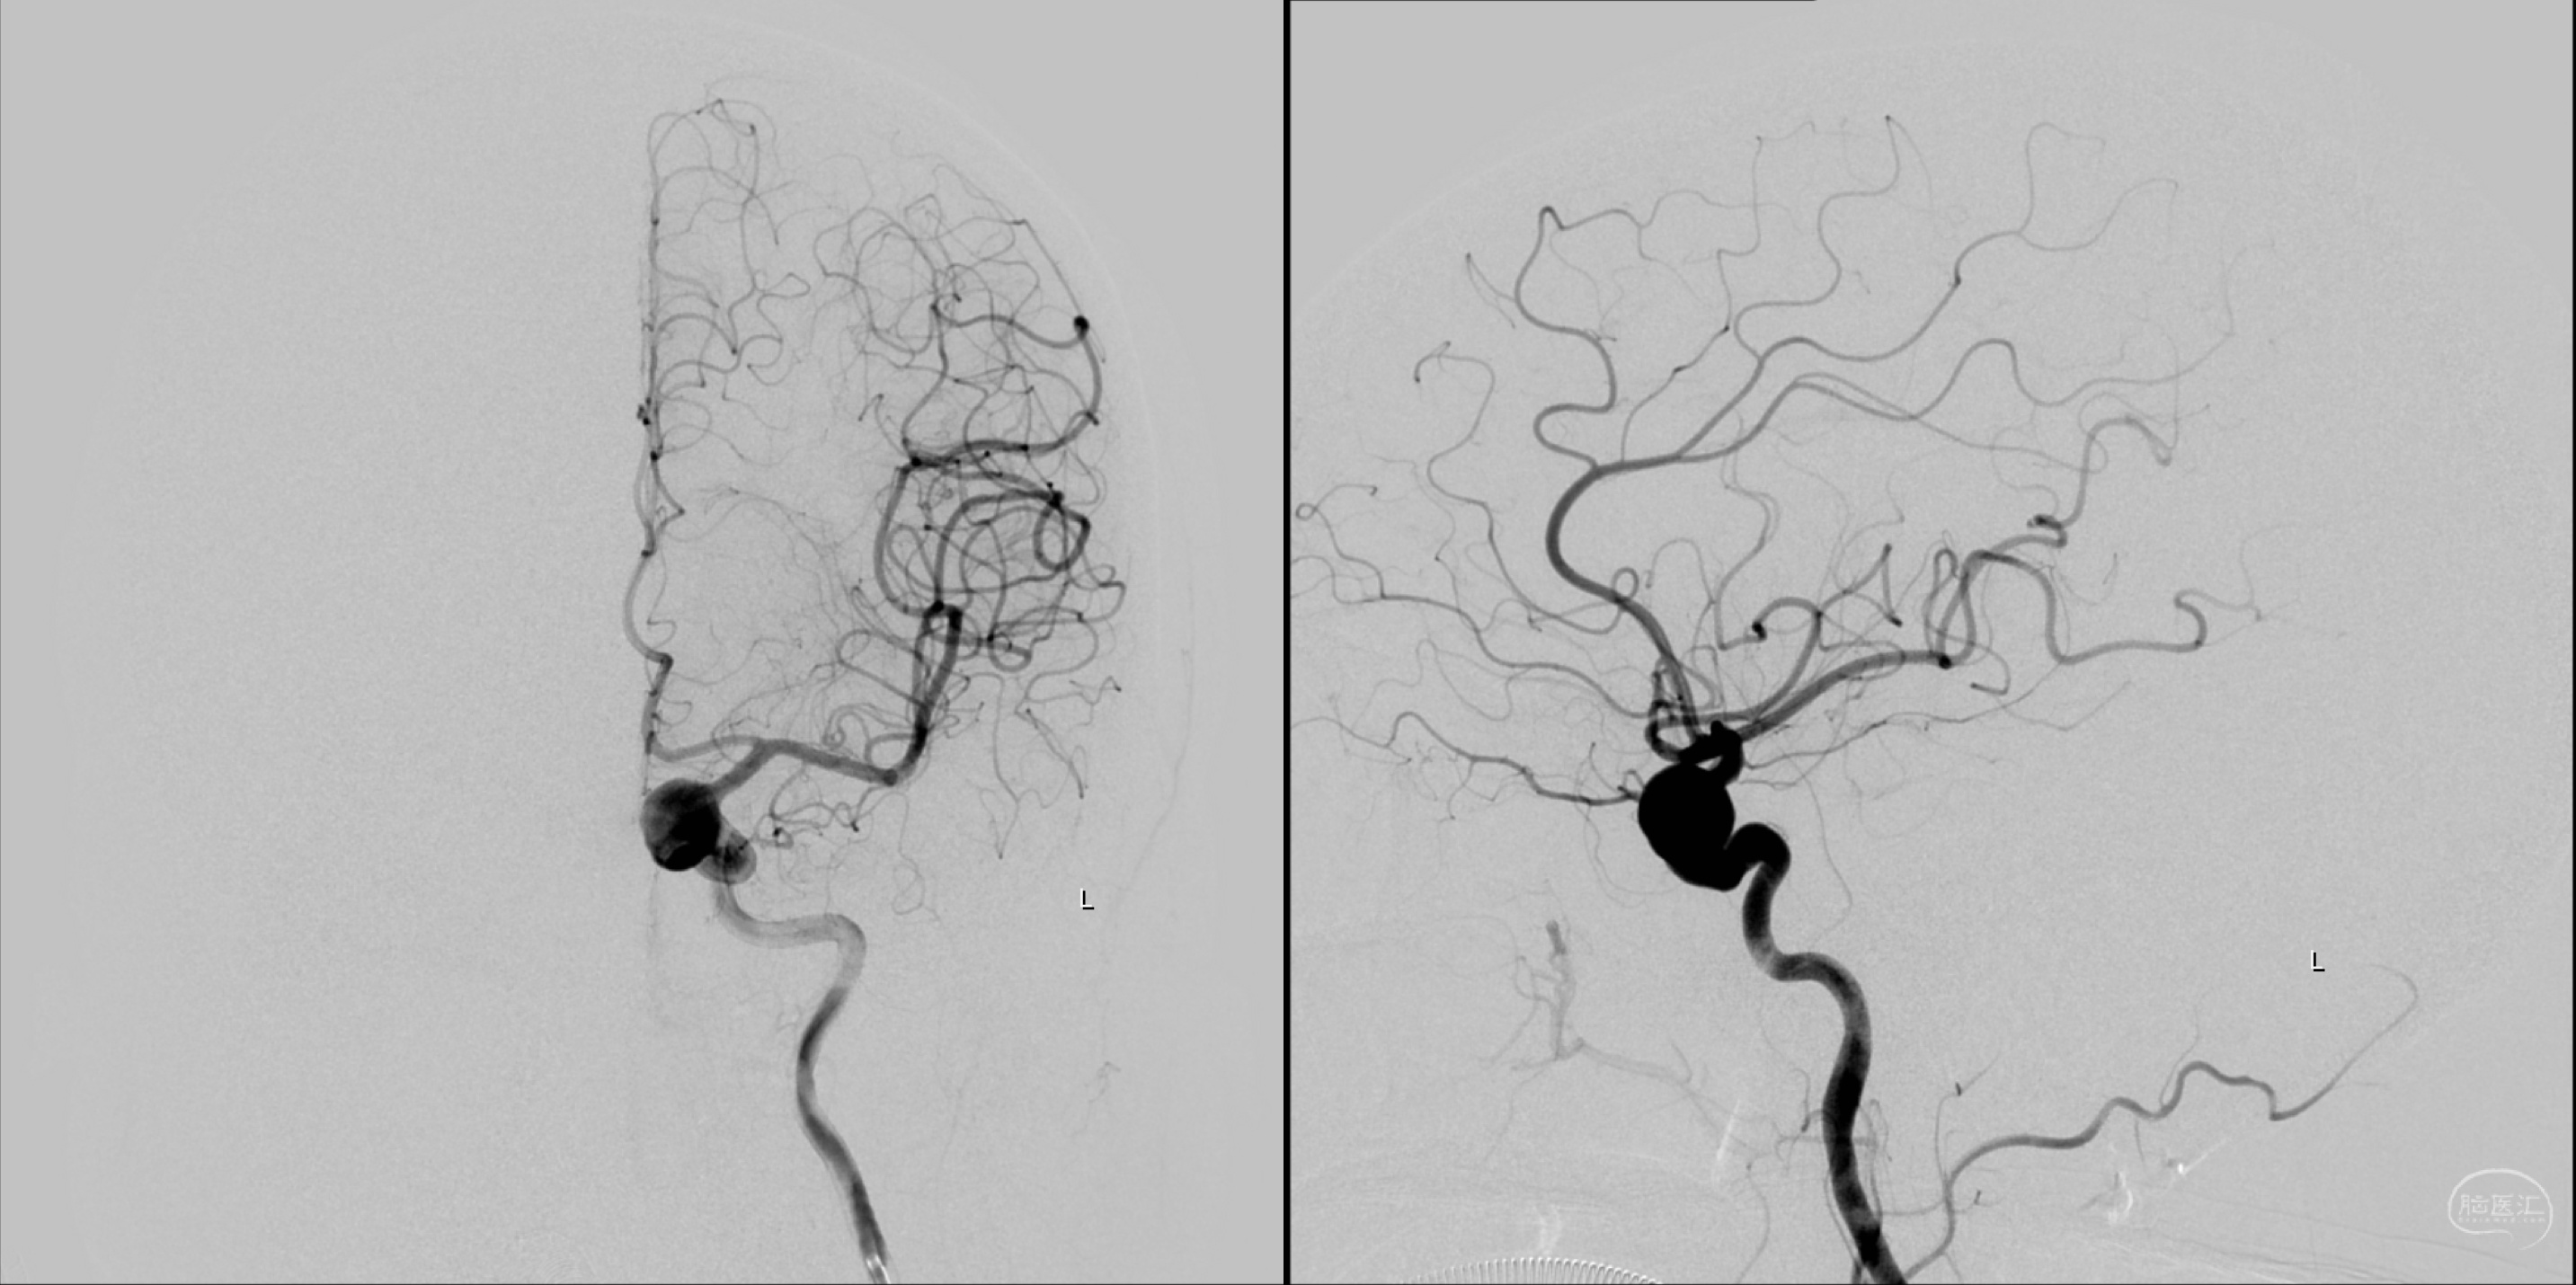

左侧颈内动脉正侧位造影:眼动脉段动脉瘤。

左侧颈内动脉三维重建:眼动脉段动脉瘤。

左侧颈内动脉三维重建:眼动脉段动脉瘤,海绵窦段血管略扩张。